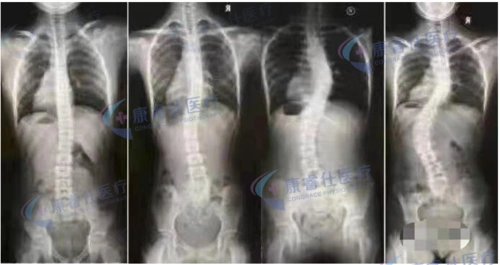

11岁少女脊柱侧弯,竟是一个姿势惹的!你可能也做过

特发性脊柱侧弯的治疗!附手术前后对比照片! - 好大夫在线